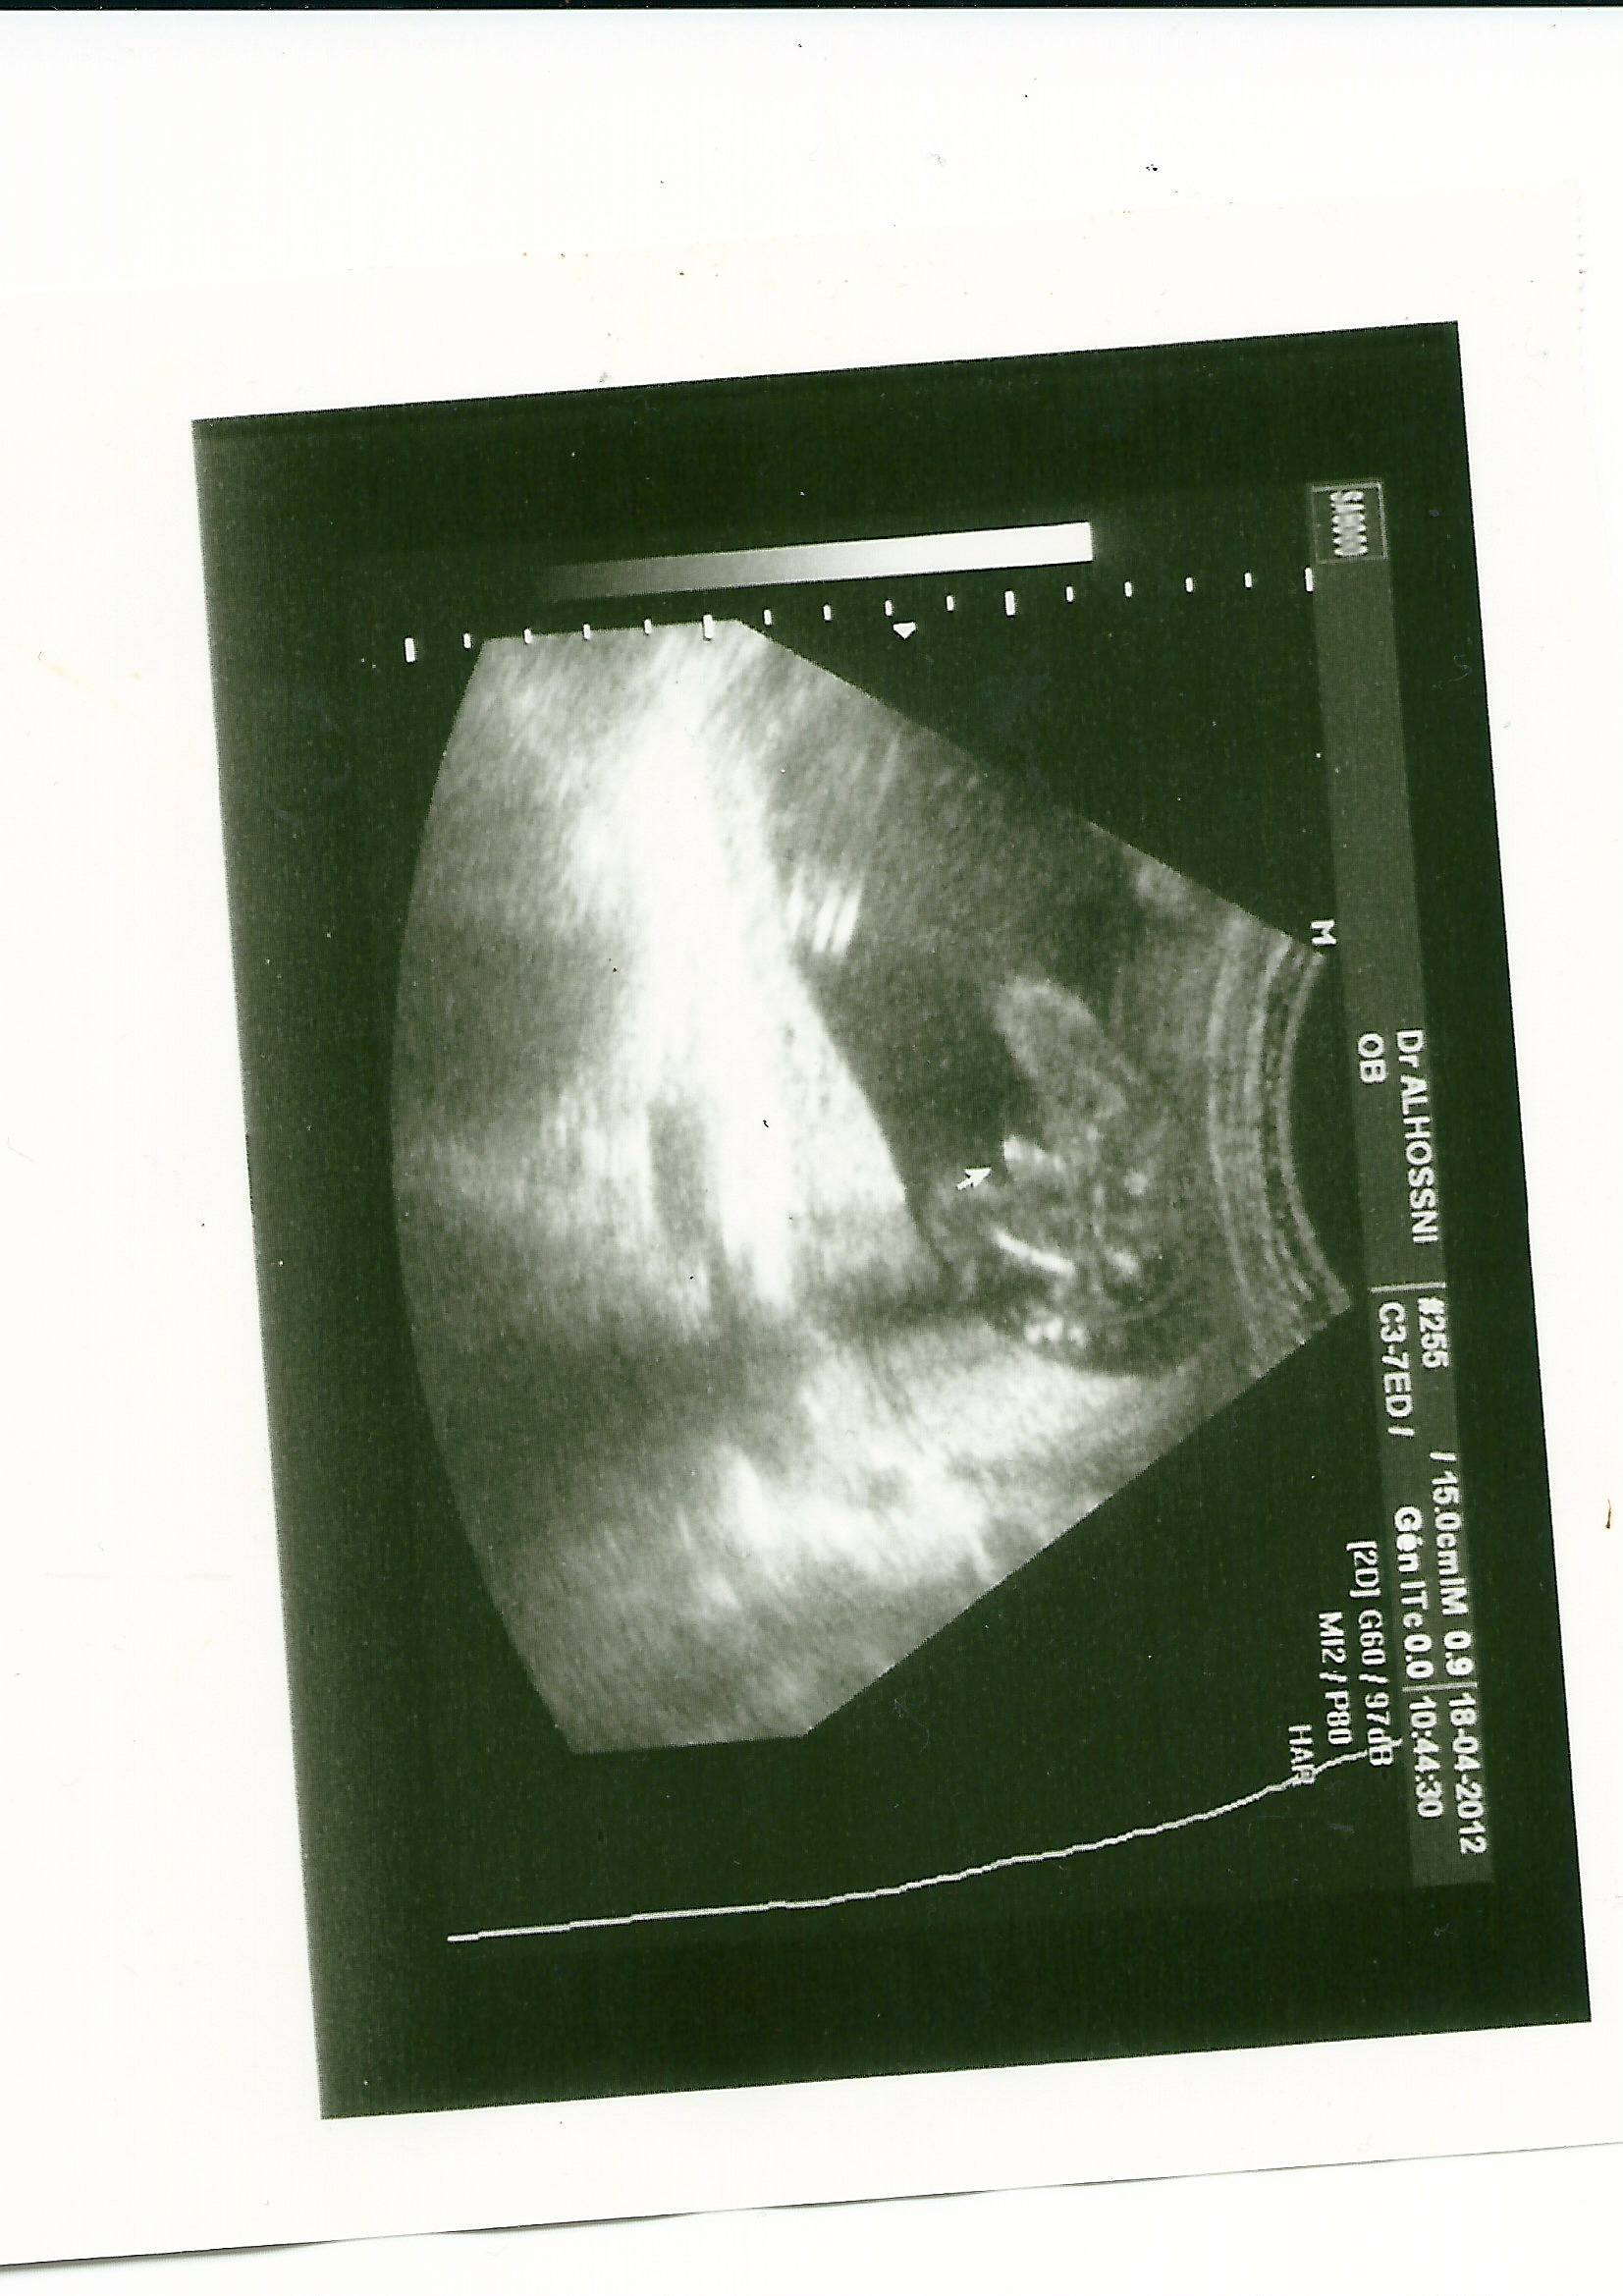

• numérisation0003.jpg

numérisation0003.jpg

261.8 KB · Affichages: 384

a 18 semaine de grossesse et si ont voit tres bien regarde sur celle en noir et blanc lendroit ou y a la fleche cest soit disant le zizi mais il me parait enormes si tu compare avec celle en 3d les 3 boules qui monte ca ressemble bien au cordon

oui pour celle en 3D cest le cordon apparremment mais a 18 semaine de grossesse tu es donc a 4 mois et demi on voit tres bien le sexe du bébé c'est vraiment rare que l'on se trompe

coucou alors pour les nouvelles je suis allez a lhopital pour des contractions mais rien de grave et linterne a regarde bien 5 minutes et elle pense que cest une fille jen peu plus jai donc un gygy a 3 mois qui me dit garcon puis a 3 mois et 3semaines mon gygy me dit filles puis a non garcon car il a vue 2 point blanc qui pour lui est les testicules puis encore echo chez mon gygy qui me dit garcon avec lecho que jai mis au dessus mais pour moi ca ressemble plus au cordon car 3 boules qui monte cest bizare pour un pti mec lol et puis maintenant cette interne qui me dit fille moi je sais plus quoi penser !!!